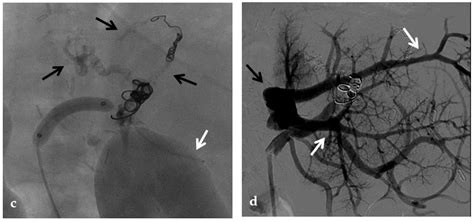

CT Angiography Provides detailed, cross-sectional images of the abdomen, clearly highlighting the thrombus and the extent of the blockage.

• Interventional Radiology: In severe, treatment-resistant cases, procedures such as Transjugular Intrahepatic Portosystemic Shunt (TIPS) may be necessary to bypass the obstructed vein and relieve portal hypertension.